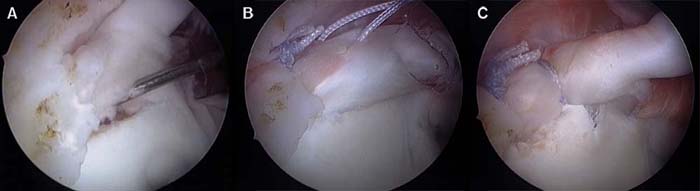

La reparación artroscópica de la lesión SLAP la realizamos en posición de silla de playa con el brazo en tracción manual por un asistente, con 30-40 de Abducción y 20 grados de flexión anterior. Con bloqueo anestésico interescalenico del plexo braquial, más sedación con infusión de propofol y con bomba de infusión continua a 30-35 mmHg. Por un portal posterior estándar para visualización, se realiza una evaluación de la unidad funcional bíceps labrum con un gancho palpador en busca de inestabilidad de la inserción del labrum superior, signo de despegamiento o peel-back, signo de drive through o paso a través. Una vez que se realiza el diagnóstico de lesión SLAP y se decide realizar la reconstrucción artroscópica, se realizan los portales accesorios antero inferior justo por encima del borde superior del subescapular y portal antero supero lateral justo por encima del tendón del bíceps, entrando a nivel del borde antero lateral del acromion. Ambos portales se realizan de afuera adentro, la localización correcta se busca mediante una aguja espinal y se realiza la colocación de cánulas de 7,25 mm con sistema de guías de dilatación progresiva (Arthrex inc. Naples Florida). La cánula antero inferior se la utiliza para manejo de sutura e instrumental y la cánula antero supero lateral para la colocación de los implantes y pasaje de sutura e instrumental. Por la cánula antero inferior se realiza el desbridamiento y cruentado de la lesión utilizando legras, raspas artroscópicas y shaver motorizado; para la preparación del lecho óseo por debajo del labrum desinsertado para mejor aporte biológico. La fijación de la lesión se realiza con arpones de titanio Fastak de 2,8 mm (Arthrex inc. Naples Florida) o preferiblemente con arpones bioabsorvibles BioSuture-Tak de 3 mm (Arthrex inc. Naples Florida). La colocación de los implantes se realiza de posterior a anterior. El primer arpón se coloca con guía de colocación del implante por la cánula antero supero lateral por detrás de la inserción del bíceps; si la lesión SLAP es muy posterior o la anatomía del portal antero supero lateral, no permite llegar con ángulo correcto de colocación del implante al cuadrante posterosuperior de la glena; se realiza la colocación del implante a través del portal de Wilmington directamente con la guía de colocación del implante con técnica transtendón en la unión músculo tendinosa, sin la colocación de cánulas artroscópicas para no dañar el manguito rotador. Luego de la colocación del implante se retira la sutura que se utilizara como poste por el portal antero inferior, por el portal antero supero lateral se realiza el pasaje de sutura con técnica de suture lazo; luego se realiza el anudado artroscópico desde el portal antero supero lateral. Según el tipo de lesión SLAP se realiza la colocación de 1 arpón por detrás y otro por delante del tendón del bíceps o 2 arpones por detrás de la inserción del bíceps. Para constatar la estabilidad de la reconstrucción, debemos corroborar la corrección del signo de despegamiento o peel-back y del signo de paso a través o drive through (Figura 5) (Ver video en pagina web).

Figura 5: A: Jugador de Rugby 20 años con SLAP tipo II combinado. B: Combinación de punto vertical y horizontal de 2 arpones por detrás de la inserción del bíceps. C: Resultado Final 2 arpones por detrás del bíceps y 1 arpón por delante del bíceps.